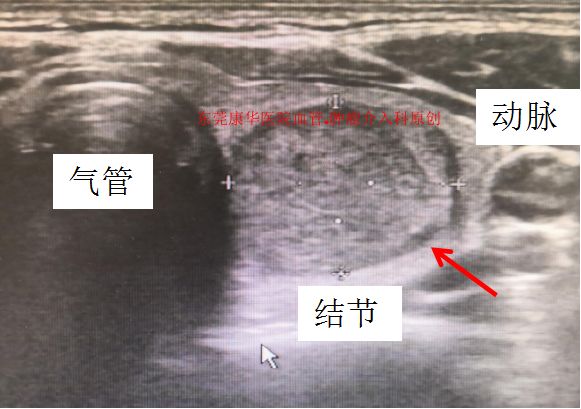

甲状腺结节的超声影像

甲状腺结节经常表现为颈部可触及的肿物

精确定位减少误伤,图为不到1cm的结节也能准确穿刺